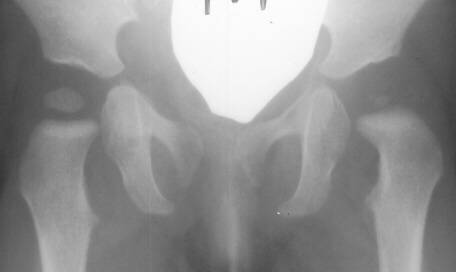

A ten year old female presented with a left hip dislocation. She was born by Cesarean-section because of slow progression of labor. The child was not breech and was noted to have a dislocatable hip at birth. There was a negative family history of DDH. An X-ray prior to application of the brace showed the dislocation of the hip. The patient was first seen at AIDI on 9th day. Abduction of the right hip was 80 degrees but left was only 60 degrees. There was a positive Galeazzi sign with the left hip being shorter than the right. X-rays showed a left hip dislocation and right hip subluxation . A Pavlik harness was applied. After two months, the right hip improved but the left hip was still dislocatable. For this, home traction was started. Even after 2 months, the left hip did not reduce. Therefore, an arthrogram, adductor tenotomy and closed reduction was done at 4 months of age. Single hip spica was applied with the hip in 40 abduction and 100 flexion. Eight weeks later an arthrogram was performed and the cast was reapplied with the hip in 35 degrees abduction and 100 degrees flexion.

Four months later, the spica cast was removed and an Atlanta brace was applied. X-rays showed avascular necrosis at ten months of age . At two years of age, the ossification of the left nucleus was still delayed. The leg lengths were equal and the range of motion of the hip was full.

The progression of the hip is documented by x-rays taken at 1 year of age, 2 years of age, 3 years of

age, 5 years of age, 7 years of age, then at ten years of age, early closure of the lateral portion of proximal growth plate observed. Coxa valga was also observed.